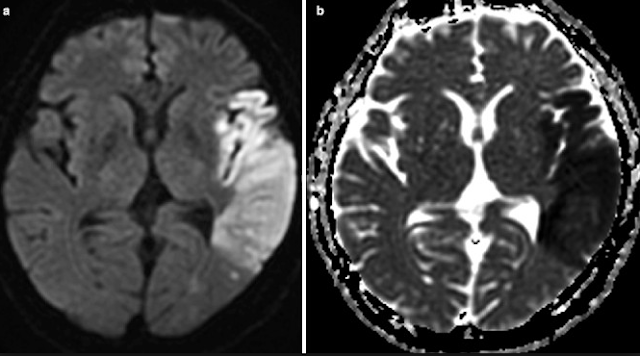

cas n°2

2- Méningiome du sinus caverneux droit